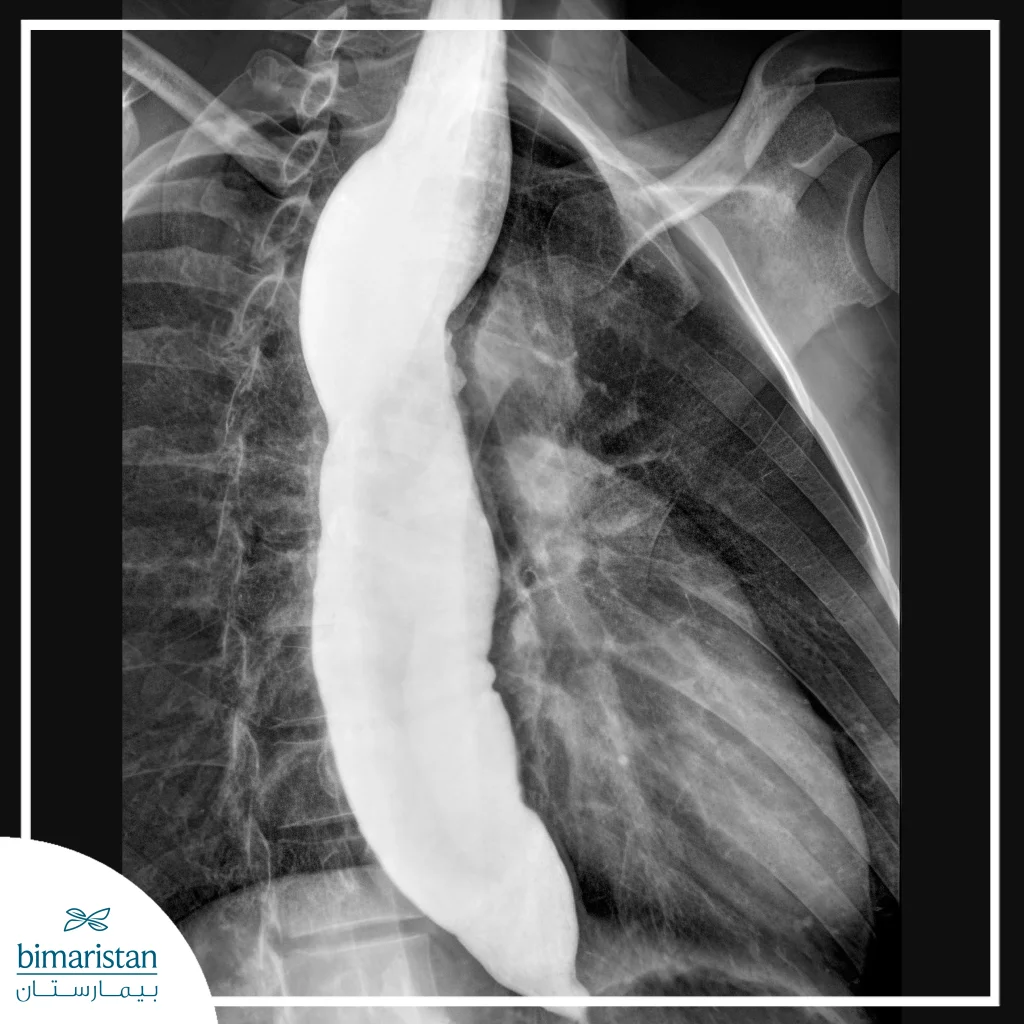

الأشعة السينية والباريوم

يتم استخدام الأشعة السينية مع الباريوم كاختبار تصويري مكمل لتشخيص تضيق المريء. حيث يقوم المريض ببلع سائل الباريوم، وهو مادة ظليلة تظهر بوضوح على الأشعة، مما يسمح برصد شكل المريء والتضيق ومكانه. هذا الفحص مفيد لتحديد طول التضيق وشدته، إضافة إلى اكتشاف أي تشوهات أو اضطرابات في حركة المريء.